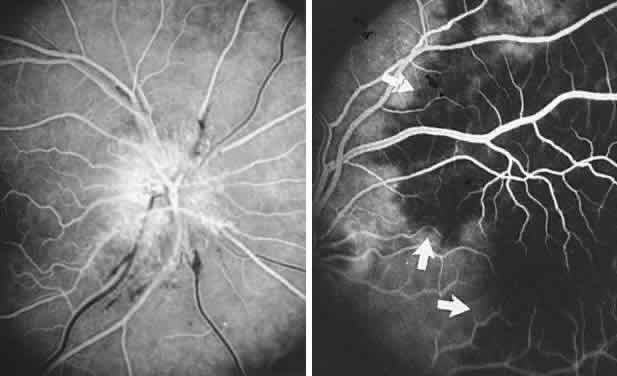

The retinal variety may be admixed in a person who suffers the more conventional attacks of migraine. It is presumed that vasospasm in the retinal circulation determines transient hypoxia, perhaps somewhat similar to the visual cortical event. On rare occasions, the fundus has been examined during typical retinal migraine episodes, and arterial constriction has been described. Wolter and Burchfield106 photographically documented such an episode and demonstrated mild “retinal edema”; vessel narrowing is also evident (Fig. 8). Fortunately, permanent complications of retinal migraine are rare. These may take the form of central retinal artery occlusion or ischemic papillopathy (see Volume 2, Chapter 16); nerve fiber bundle visual field defects may be demonstrated (Fig. 9).

Fig. 8. Retinal migraine. A. During amaurotic episode. Note the dusky appearance of the fundus, increased retinal sheen (possibly edema), and dark narrowed veins (arrows). The disc is also hyperemic. B. Fundus after episode. Compare paired arrows. (Courtesy of Dr. J. Reimer Wolter)

Fig. 9. An 18-year-old student with recurrent episodes of left retinal migraine. After a typical attack, he noted an inferior field defect. A. Fundus shows a defect in the superior arcuate nerve fiber bundle (between arrows: compare fiber layer below disc). B. Visual field defect corresponds to a retinal nerve fiber layer defect.